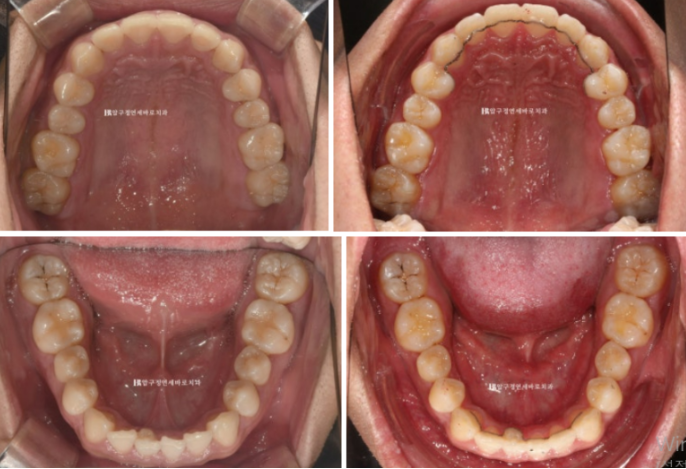

The upper teeth are aligned,

24.02

but one of the lower front teeth is crooked.

In particular, one of the lower front teeth shows an abnormal tooth shape.

The protruding part at the back is part of the tooth.

24.07

The bite after wearing all 14 aligners for 4 months.

The patient diligently wore the elastics in the blue-arrow area, and over 4 months the tilted occlusal plane and deep bite were successfully corrected.

24.02-24.07

As the deep bite was relieved, the lower teeth are now visible when biting down.

The crooked front teeth became aligned, and a wire retainer was made to match the area of the abnormal lower front tooth.

A fixed retainer is essential.

24.02~24.07

These are the changes over 4 months with Invisalign Lite.

The patient’s excellent cooperation, the use of orthodontic mini-screws,

and an appropriate treatment plan created good results in a short period.